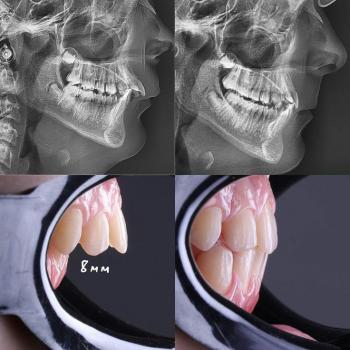

The infection from his severe cavities isn't staying put. It’s traveling down the roots of his baby teeth and directly attacking the developing enamel of his permanent teeth. The consequence?

Weak Foundation: The adult teeth may erupt already discolored (yellow or brown) and weak, prone to cavities from day one.

Misalignment: Baby teeth act as placeholders. If Jaime’s teeth are extracted early or lost to decay, the adult teeth will erupt crooked, crowded, or even impacted, leading to complex orthodontic issues later.